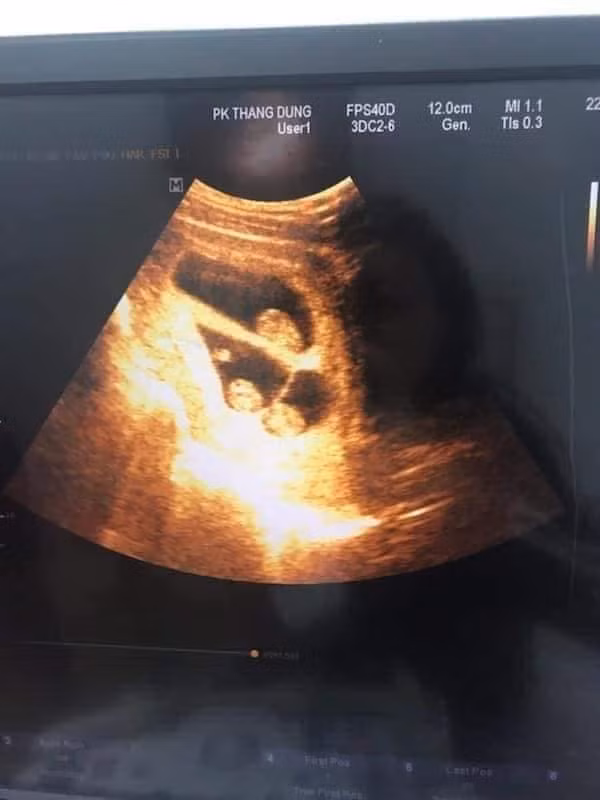

Mới đây, trên mạng xã hội lan truyền bài viết của một ông bố với tựa đề "vợ sinh ba là cảm giác như thế nào" khiến nhiều người quan tâm. Anh chồng chia sẻ khi siêu âm nghe 3 tim thai, anh "sướng rơn người".

"Tôi thề là thích lắm các bác ạ, lúc đi siêu âm nghe bác sĩ báo có 3 thiên thần thôi mà sướng rơn người. Trước mình cứ nghĩ muốn sinh ba phải can thiệp kiểu chuyển phôi thì mới có ai dè mình lớ ngớ vớ huy chương luôn. Vừa viết mà vừa cười miệng rộng ngoác ra đây." - Anh Đông vui vẻ chia sẻ lại cảm giấc lâng lâng khi làm bố.